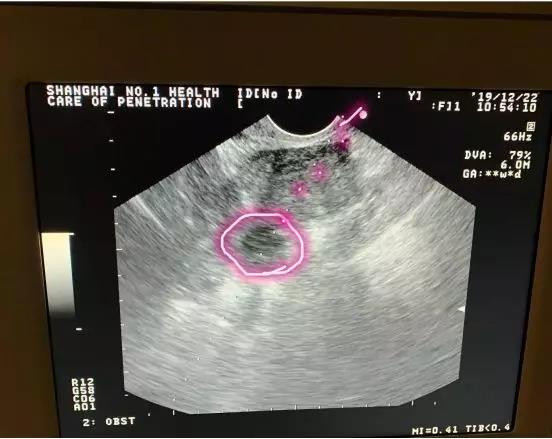

而这种情况,取卵针要经过子宫,长途跋涉后才能刺入卵泡,那肯定疼,我给你取卵也会疼!